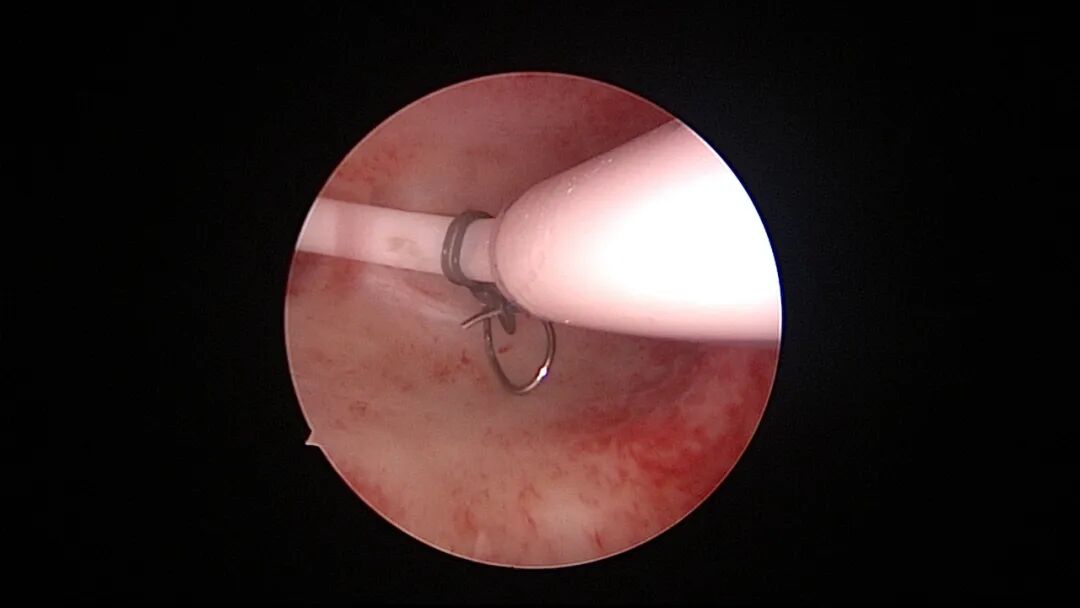

操作步骤描述:宫腔检查镜可完成操作,扩张宫颈至7号扩宫棒,检查镜能轻松通过,避免镜鞘与节育环纵臂在宫颈管形成卡压及筷子效应,影响操作,或卡压摩擦阻力大带出节育环。可用单级电针在宫底扎出小凹坑做标记或作为置入挂钩的隧道(不是必须的)。将挂钩用异物钳直视下送入宫腔,或用中弯钳盲视下送入宫腔,异物钳夹持挂钩将倒钩端插入宫底肌层,越过倒钩。用环尾丝或不可吸收线在节育环顶端打结,形成一个线圈,直径约0.5cm~1cm,结打在线圈旁边,便于夹持操作。将环装回推杆送入宫腔,再夹住节育环固定线圈抵紧宫壁稍旋转就可以将线圈滑进挂钩缺口,挂到挂钩上,可再次向宫底推送挂钩少许,不必夹闭挂钩缺口,重力作用和内膜生长都会阻止线圈脱出,可以用电针电凝挂钩周围组织,进一步防止挂钩脱落。异物钳原位固定节育环,退出宫腔镜,距宫颈外口0.5cm~1cm剪断剩余尾丝。宫颈扩张到9号扩宫棒,冷刀系统异物钳夹持挂钩及线圈也可完成以上操作。

取胚术后丝线挂钩固定节育环图片及视频

子宫腺肌症内膜息肉切除后丝线挂钩固定曼月乐并电凝图片及视频

异常子宫出血内膜增生节育环尾丝挂钩固定曼月乐图片及视频